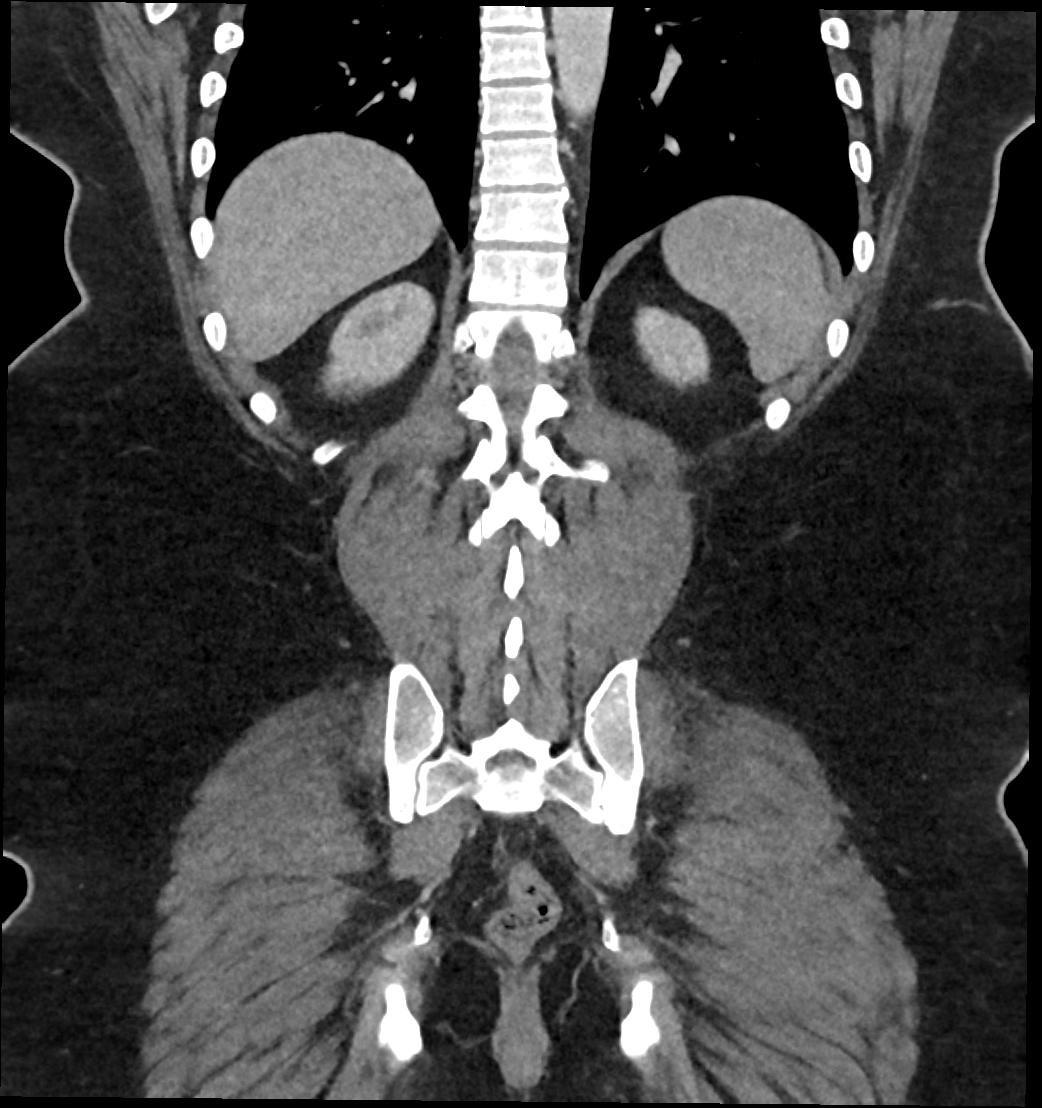

Patient: Padmakumar A. , *1988-04-24, PID: 3000069741773230809

Study Description: CT ABDOMEN

Image Series: Abdomen Cor 3mm [4]